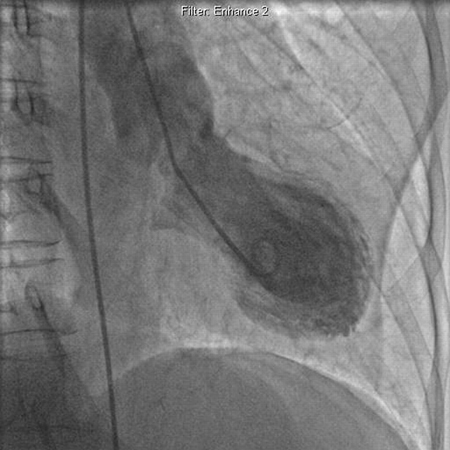

Left ventriculogram demonstrating apical ballooning in tako-tsubo cardiomyopathy

Augustine DX, Domanski A, Garg A. The stress of chest pain: a case of tako-tsubo cardiomyopathy. BMJ Case Reports. 2009; doi:10.1136/bcr.03.2009.1660